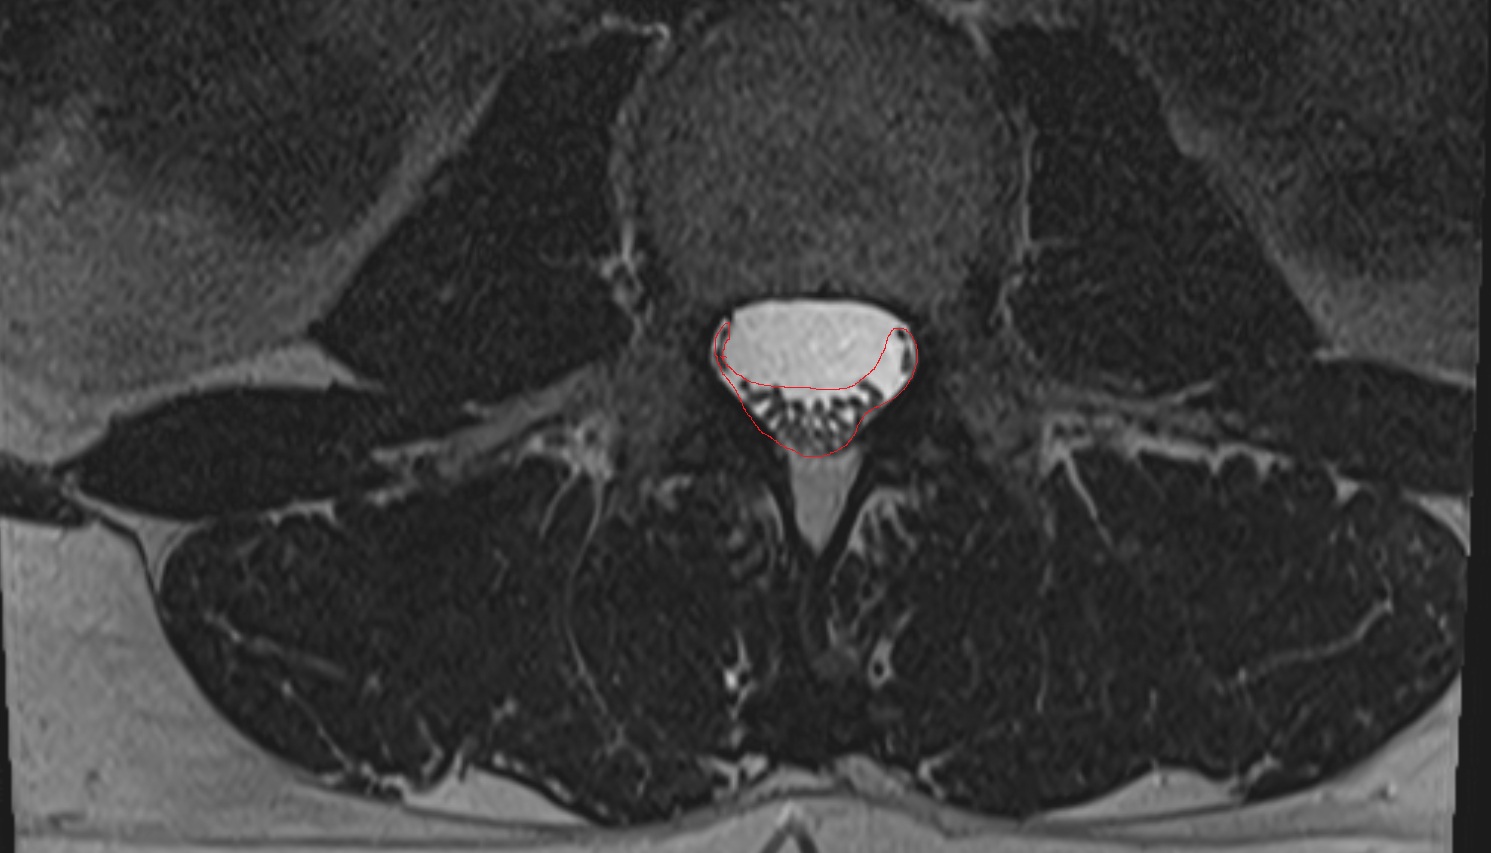

- Cauda equina

- Conus medullaris

- Spinal dura mater

- Spinal epidural space